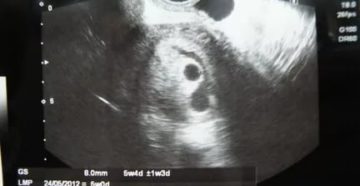

Деформированное плодное яйцо на ранних сроках беременности Здравствуйте, дорогие читатели блога! Вы слышали, что плодное…